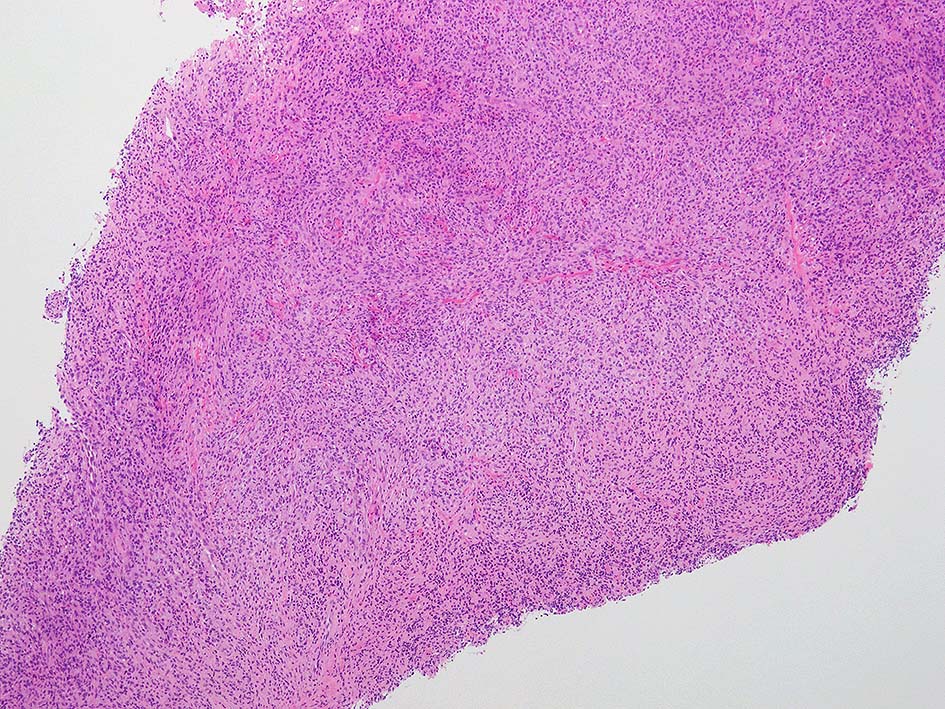

loupe像:表面に痂皮形成. 均等な組織像で,壊死や出血はみられない. 低倍ではspindle cellの密な増殖があるように見える. 拡大所見では, 類円形, 卵円形, ねじれた桿状の核, くびれ,勾玉様の核など不整形な核をもつ細胞が増殖している. クロマチンは繊細な傾向で, 核小体を1個もつ核が認められる. 高倍率10視野で 1-2個の核分裂像が数えられた.

樹状細胞性腫瘍, 組織球性腫瘍, histiocytic sarcoma(あまり異型がめだたない)などを考えて鑑別, 免疫染色をおこなった.